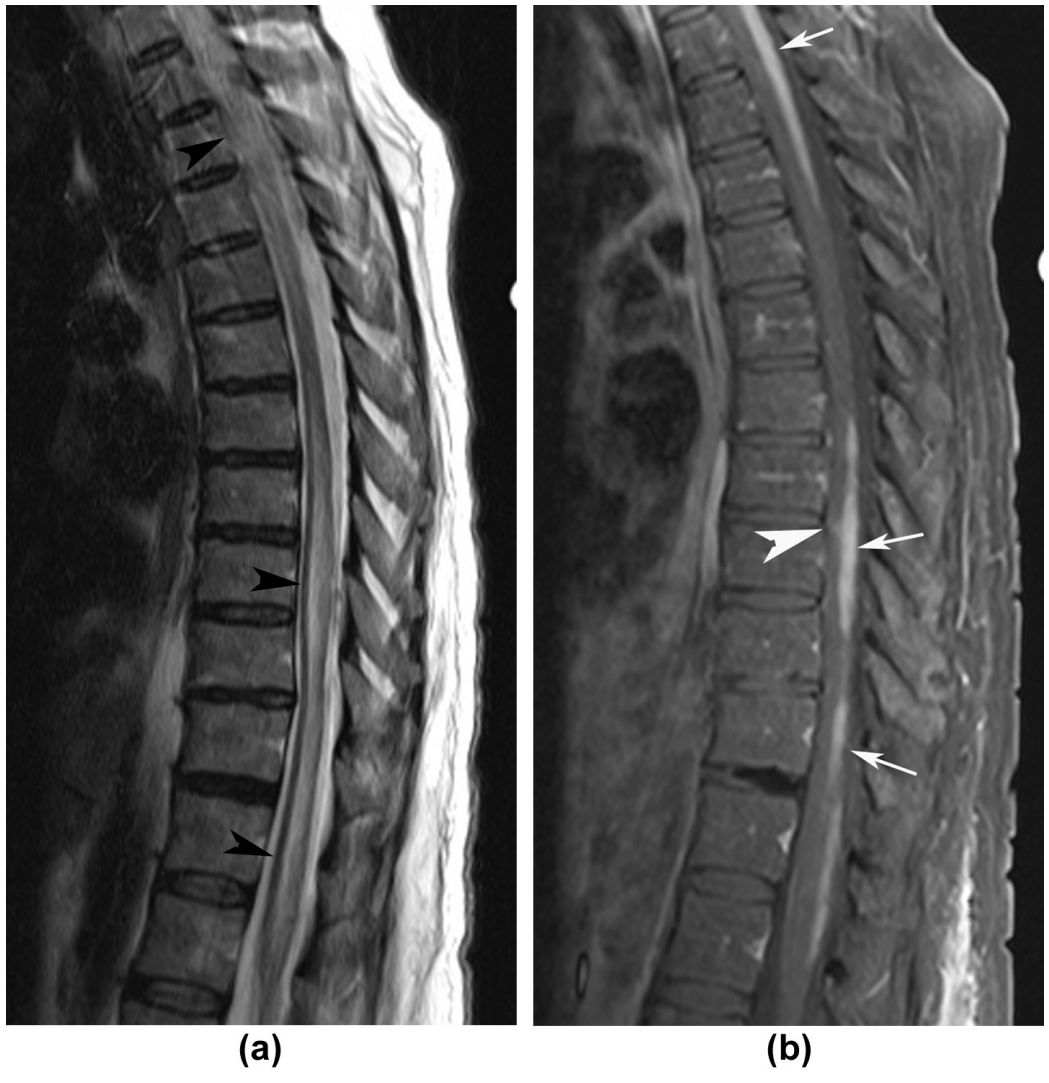

➤脊髓受累: